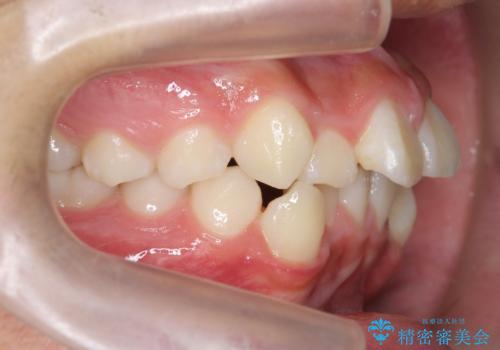

- 前歯のがたつきが原因で歯ブラシしづらい、見た目を改善したい!と矯正治療を希望され来院されました。

スペースの不足が見られるため、小臼歯の4本抜歯を行いマルチブラケットを用いた矯正治療を計画します。